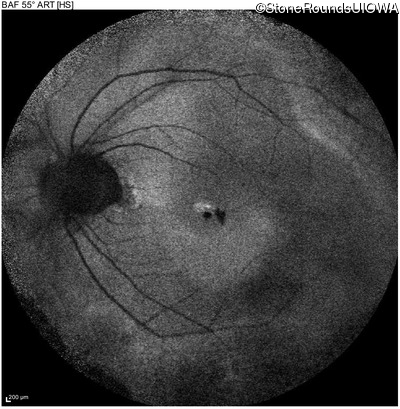

Blue Autofluorescence - Right - 20/25

Exemplar

Blue Autofluorescence - Left - 20/40 +1